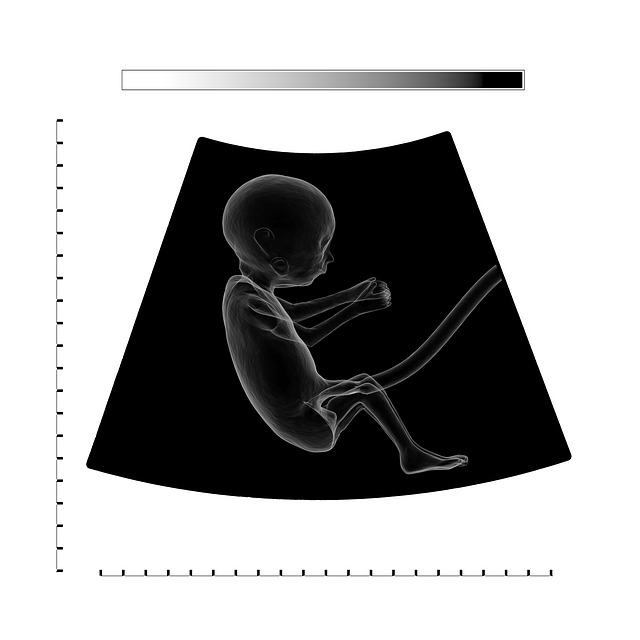

Ultraschall zeigt Zwilling

Glückwünsche sind angebracht, wenn zu diesem Zeitpunkt ein Ultraschall zeigt, dass Sie nicht nur ein, sondern zwei (oder mehr!) Babys tragen. Was für ein Segen es ist, Zwillinge zu haben. Lesen Sie weiter, um herauszufinden, wie Sie feststellen können, ob Sie zweieiige oder eineiige Zwillinge bekommen und was Sie in jeder Schwangerschaftswoche erwarten können. Und wenn Sie auf dreimal so viel Aufregung hoffen, lernen Sie alles über das Tragen von Drillingen.

Können Sie mir sagen, wie ich die aufgenommenen Ultraschallbilder speichern kann?

Ihr Kind zum ersten Mal im Mutterleib zu sehen, ist ein unvergessliches Erlebnis. Leider altern Ultraschallbilder schlecht. Stellen Sie sicher, dass Sie ein digitales Foto von sich machen, wenn Sie Wert darauf legen, es für die Nachwelt aufzubewahren. Manchmal bieten Ultraschalltechniker sogar an, Ihnen digitale Kopien der Scans per E-Mail zu senden. Sie können auch auf Websites wie Pinterest oder Etsy suchen, um einzigartige Speicher- und Anzeigeoptionen für Fotos zu finden.